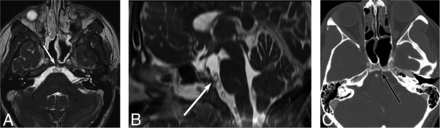

A previously healthy 16-year-old girl underwent MR imaging for headaches. The examination findings were normal except for a well-defined 5-mm T2-hyperintense prepontine mass with a dark rim and clival extension (Fig 1). A CT was performed for further characterization, showing a well-defined sclerotic margin to the clival component. There was no associated enhancement or mass effect. The interpreting radiologist stated that the lesion presumably represents ecchordosis physaliphora, and long-interval follow-up imaging was recommended.

A 16-year-old girl with headaches. A, Sagittal steady-state free precession MR imaging shows a lobular, well-defined T2-hyperintense lesion (arrow) in the prepontine cistern. Axial reformatted image (B) shows a benign-appearing abutment to the clivus. Axial CT (C) shows slight remodeling of the posterior clivus without erosion.